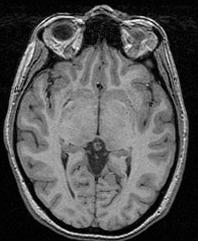

This procedure relies on the fact that the brain is a light and massive object surrounded by a black strip related to the skull, which largely isolates it from the other tissues. The image analysis procedure aims at splitting the few connexions between the brain and the external world using an erosion process very similar to geological phenomena or to the action of the rust, when it weakens metallic objects at the level of their bottlenecks before breaking them.

The grey level image is thresholded first in order to get a binary object (white on black background). During a second stage, an erosion process is simulated in order to trim the object until a given thickness. This erosion fathers several disconnected pieces. The largest one is selected as a seed of the brain. A dilation process makes the seed growth in order to recover the actual brain shape.

An illustration of the process at the level of a slice:

You can for instance visualize simultaneously the bias corrected image and the brain mask, relying on Anatomist linked cursor:

Another way consists of the two volume fusion. brainVISA's eye can do it for you. If you prefer manual work, select the two volumes, give a unicolor colormap with the ufusion extension to the mask, and choose the linear combination fusion mode: